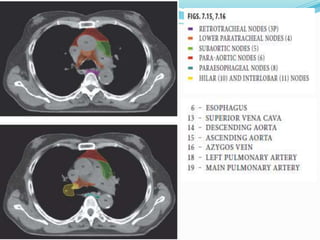

The International Association for the

Study of Lung Cancer Lymph Node Map: A

Radiologic Atlas and Review

 14 LN stations reorganized into 7 zones

 Supraclavicular zone

 Upper zone

 AP zone

 Subcarinal zone

 Lower zone

 Hilar zone

 Peripheral zone

The International Associationfor the Study of Lung Cancer Lymph Node Map: A Radiologic Atlas and Review  14 LN stations reorganized into 7 zones  Supraclavicular zone  Upper zone  AP zone  Subcarinal zone  Lower zone  Hilar zone  Peripheral zone